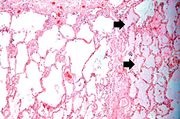

| 16:08, 19 August 2013 | IPLab4PulmonaryCongestion5.jpg (file) | 63 KB | Seung Park | This is a higher-power photomicrograph of lung. The edema fluid within the alveoli is visible at this higher magnification (arrows). The thickened pleura (1) is on the left. | 1 | |